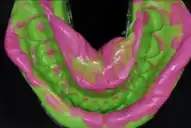

A dental impression is a negative imprint of hard and soft tissues in the mouth from which a positive reproduction, such as a cast or model, can be formed. It is made by placing an appropriate material in a dental impression tray which is designed to roughly fit over the dental arches. The impression material is liquid or semi-solid when first mixed and placed in the mouth. It then sets to become an elastic solid, which usually takes a few minutes depending upon the material. This leaves an imprint of a person's dentition and surrounding structures of the oral cavity.

Vinyl polysiloxane impression material (impression material)

vinyl polysiloxane dental impression materials used for making accurate dental impressions with excellent reproducibility. It is available in Putty and light body consistencies to aid dentists make perfect impressions for fabrication of crowns, bridges, inlays, onlays and veneers. Example Flexceed